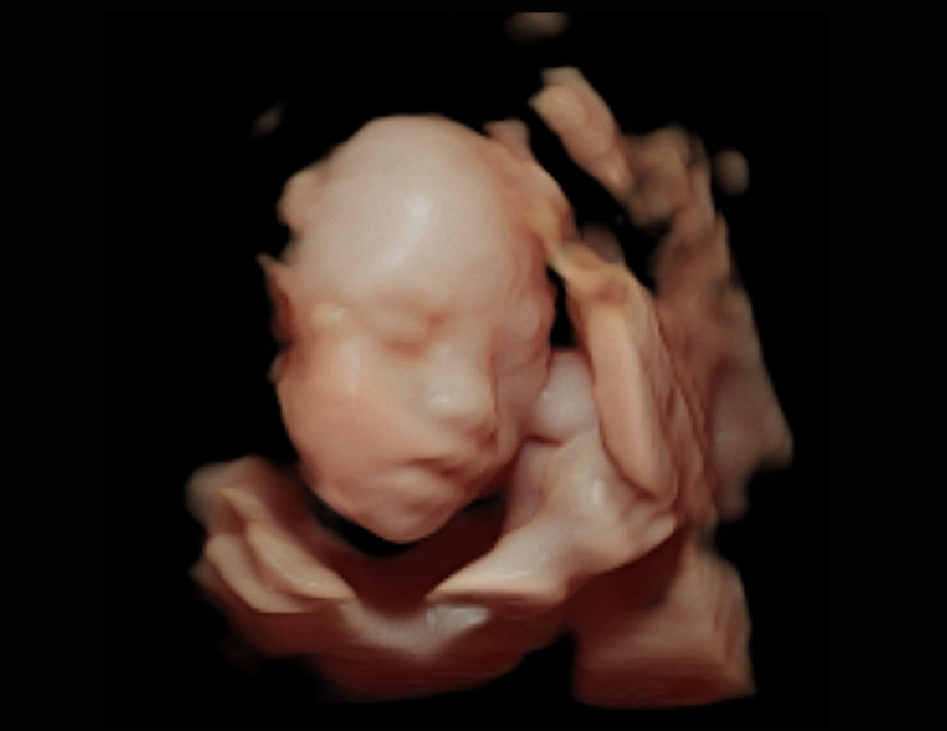

在4D模式下,启用高清成像功能后,智能可变光源系统即可通过虚拟光源位置的改变,使常规容积成像的图像加以增强、高亮显示。